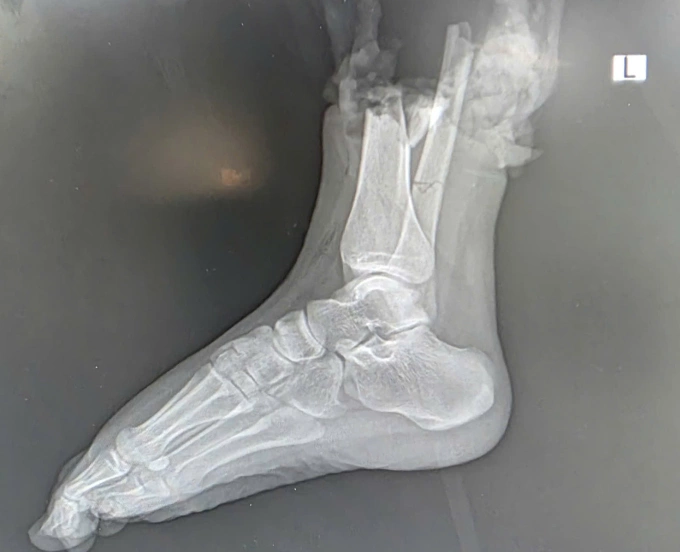

Hình ảnh chụp phần chi thể đứt rời. Ảnh: Bệnh viện cung cấp

Trước đó, khoảng hai giờ sau cú va chạm với môtô phân khối lớn trên phố Trịnh Văn Bô tối 16/10, nữ sinh quê Bắc Ninh được chuyển đến Bệnh viện 108 trong "thời gian vàng". Các bác sĩ xác định phần cẳng chân phải của bệnh nhân bị đứt lìa, tổn thương phức tạp kèm dập nát phần mềm.